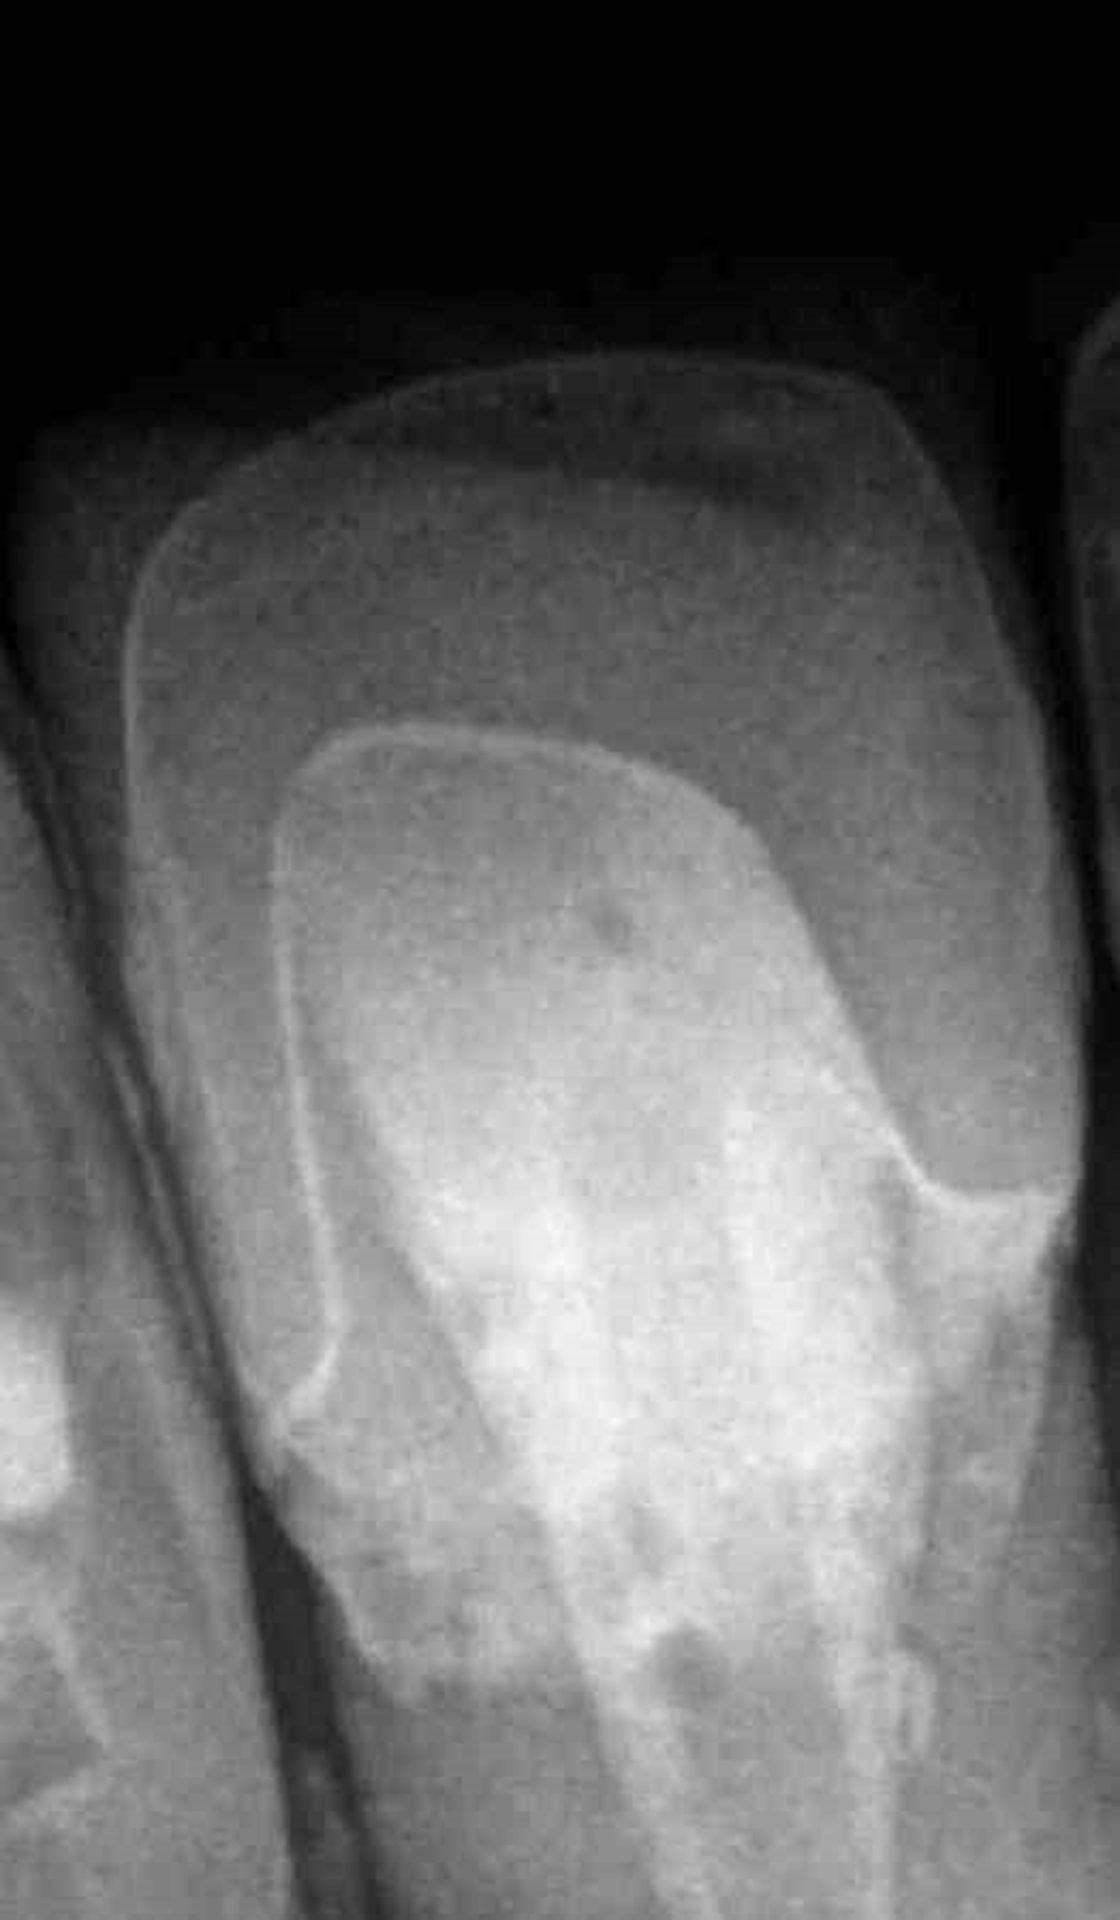

Через три дня после повторной гидратации зубов пациентка была приглашена на контрольный приём. Отмечено заживление мягких тканей после процедуры фиксации. Также был зафиксирован приемлемый цветовой результат и гармоничное сочетание керамических виниров с окружающими тканями (рисунки 11 и 12). Рентгеновский снимок зуба 21 представлен на рисунке 13.

Рис. 13. Рентгенограмма зуба 21 после фиксации.